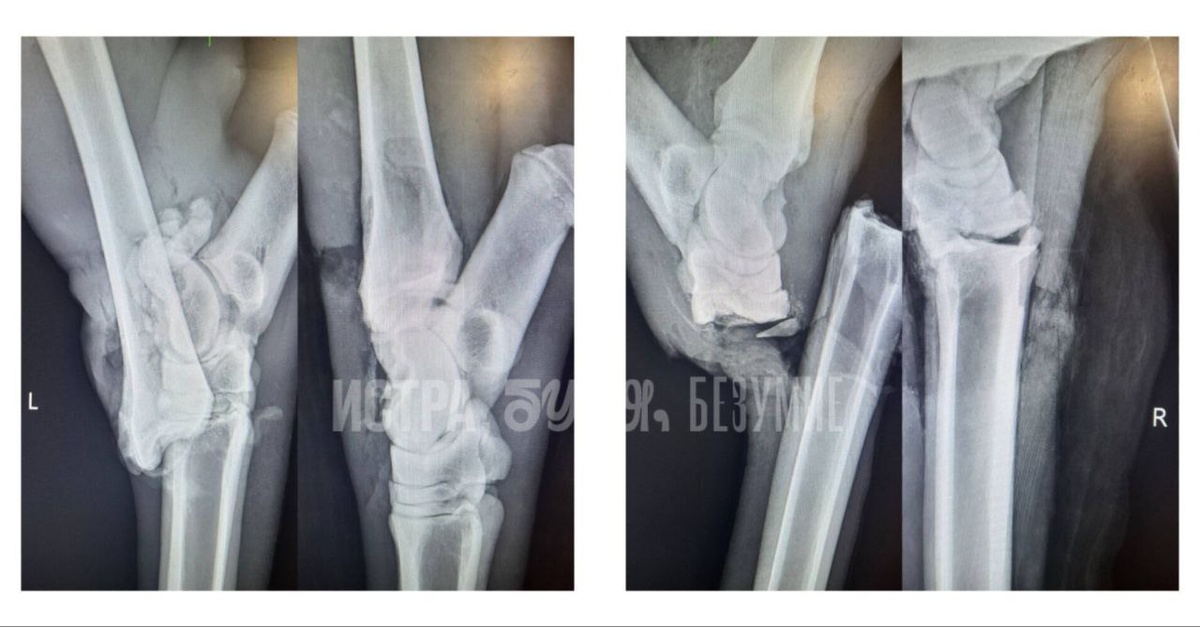

Ветеринары оказали помощь сбитому в Подмосковье лосю. Сегодня ему должны провести операцию.

Животному уже лучше: температура тела поднялась с 35° до нормы, раны обработаны, наложен временный гипс. Во второй половине дня врачи собираются провести ему операцию на ногах.

По словам специалистов, состояние у лосенка стабильное, но впереди его ждет долгий путь к восстановлению.